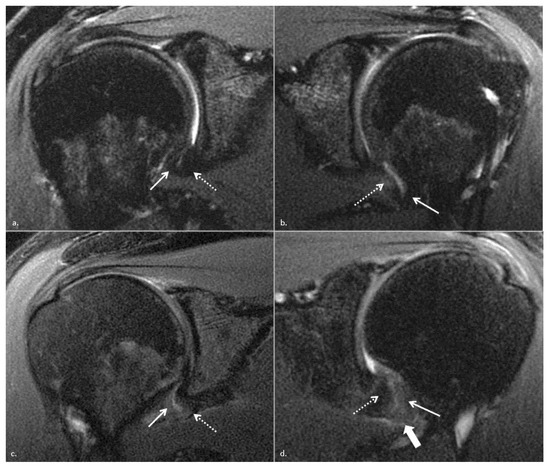

2.5. Image Analysis

- 1: normal homogenous low signal intensity

- 2: partial or foci of signal hyperintensity

- 3: global signal hyperintensity

- 4: linear hyperintensity of the peri-articular soft tissues